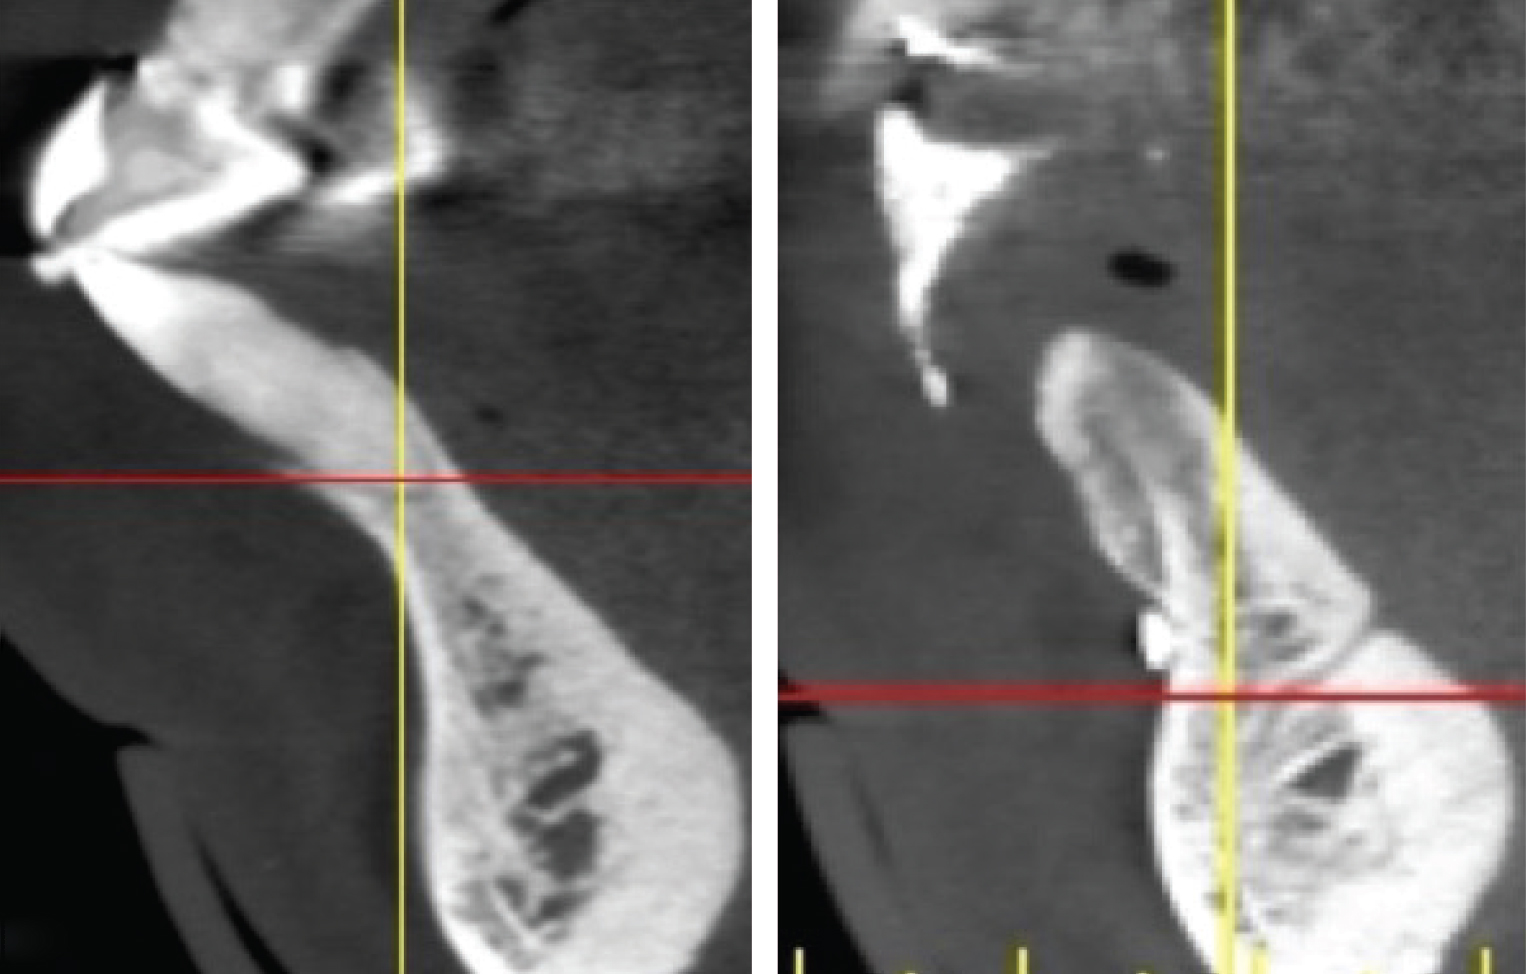

(Left) An example of a mandibular anterior tooth, No. 27, that was treated with extraction and replacement with a single implant. Note the concavity in the alveolus apical to the tooth. There was inadequate apical bone for extraction and immediate implant placement, thus

a 2-stage surgical approach was planned. In this case, had only the socket been  lled with grafting material there still would not have been enough bone present for proper implant placement. A full-thickness  ap was created and GBR performed to both preserve the site and correct the apical de ciency for implant placement. (Right) Note the new bone formed buccal to the ridge and the bone now available for implant placement.

The shape and amount of bone present apical to the extraction socket is the apical topography and is important in treatment planning for both immediate and delayed implant placement. For immediate implant placement, the apical topography is significant, as 3 mm to 4 mm of native bone needs to be engaged for primary stability of the implant.1,2 If planning a 2-stage approach with site preservation and delayed implant placement, analysis of the apical topography is also essential. If a tooth with an apical concavity is extracted and a graft is placed only inside the socket, there may not be adequate bone following healing to place the implant in the proper position without additional surgical procedures3 (Figure 2). Teeth that do not have enough apical bone to provide the housing necessary for immediate implant placement or delayed implant placement with grafting inside the socket alone are defined as having inadequate apical topography. This inadequacy can be the result of periapical pathologies or the anatomy of the alveolus.